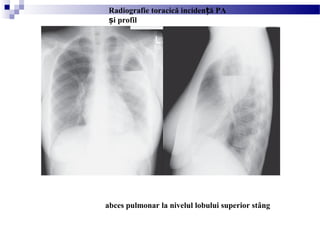

abces pulmonar la nivelul lobului superior stâng

Radiografie toracică inciden ă PAț

i profilș

CT torace

(abces pulmonar cavitar la nivelul lobului superior stâng)